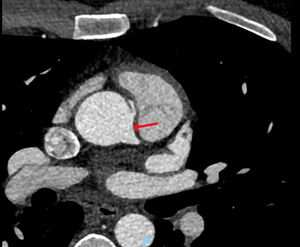

Case presentationsCase 1A 37-year-old male athlete, presented to the hospital for a sport's physical examination. Despite having no clinical symptoms, an ST segment depression was found in the inferior and precordial leads during a cardiopulmonary stress test (maximum descent of 0.26mV at aVF). Physical examination, ECG and Doppler ultrasound presented no significant findings. A coronary computed tomography angiography was performed to further define his underlying condition. The images revealed an AORCA, which stemmed anterosuperiorly from the left coronary sinus and approximately 23mm from the aortic valve, at the level of the sinotubular junction (Fig. 1). No pathological findings were reported regarding coronary caliber or the remaining coronary branches.